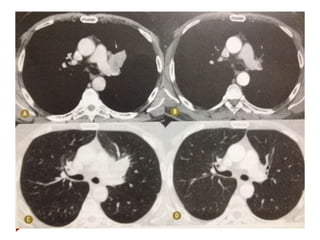

RECIST

 Definição das lesões-alvo

 Deve haver pelo menos uma lesão mensurável.

 Definir as lesões-alvo, que serão mensuradas em todas as avaliações

(mensuração de carga tumoral).

 Máx 2 lesões por órgão, e máx de 5 lesões ao todo.

 Se houver mais que 5, selecionar as maiores, representando os diversos órgãos.

 Lesões sólidas são preferíveis.

 Considerar a soma dos diâmetros das lesões (maior eixo tumores e menor para

lnds).

 Medidas realizadas no plano de aquisicão da imagem, não de reconstruções.

 Lesões não-alvo podem ter descrição genérica.

RECIST  Definição daslesões-alvo  Deve haver pelo menos uma lesão mensurável.  Definir as lesões-alvo, que serão mensuradas em todas as avaliações (mensuração de carga tumoral).  Máx 2 lesões por órgão, e máx de 5 lesões ao todo.  Se houver mais que 5, selecionar as maiores, representando os diversos órgãos.  Lesões sólidas são preferíveis.  Considerar a soma dos diâmetros das lesões (maior eixo tumores e menor para lnds).  Medidas realizadas no plano de aquisicão da imagem, não de reconstruções.  Lesões não-alvo podem ter descrição genérica.